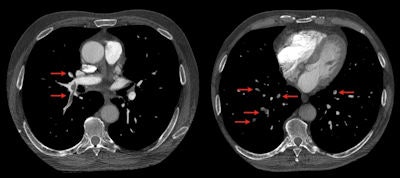

"The introduction of larger, more powerful devices (such as the iPad 2) is likely to further expand this kind of application, with some surgeons already using it in the operating room to assist interventions," Faggioni said. For instance, the following images of CT pulmonary embolism and knee MRI, as well as the chest CT image of lung nodules above were exported from an iPad 2. "Diagnosis could have been made on it without the need of a workstation," he said.